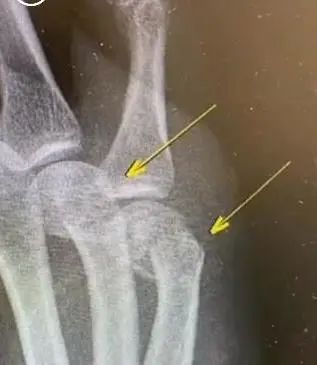

右手第四第五掌骨肿胀明显

新华医院骨科主治医师王晖

询问后得知

原来这名患者

在家辅导孩子作业时

因孩子作业做得不理想

生气但舍不得打孩子

只能自己捶墙踹墙

没想到把自己捶骨折了……

最后只能住院做手术

在手掌里打了钢板